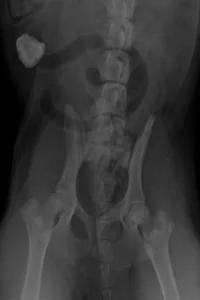

Timbertown-Vet-Swallowing-Rocks-Imaging